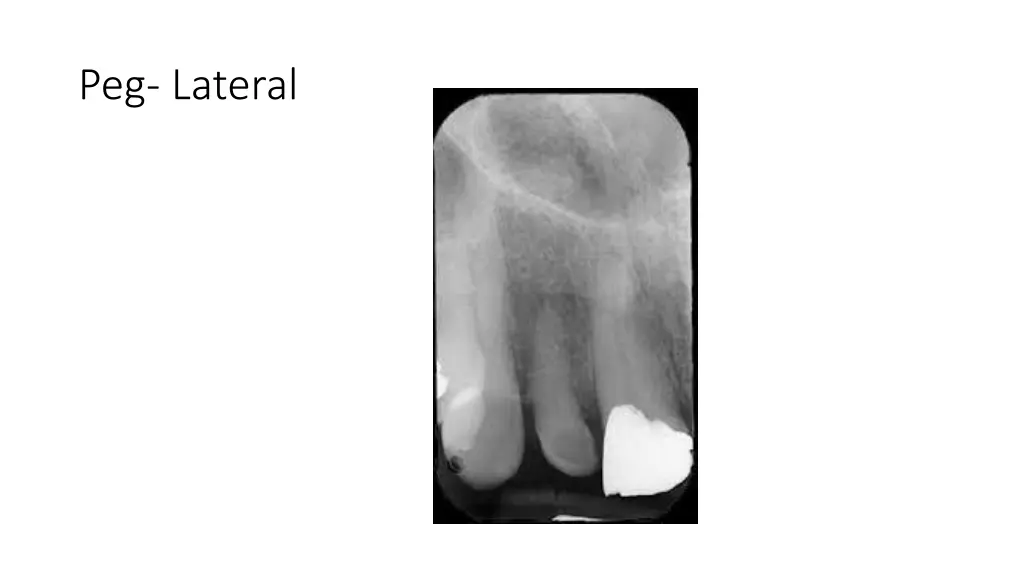

True Anodontia, Partial True Anodontia, Partial False Anodontia, Mesiodens/Supernumerary, Microdontia, Marcrodontia, Gemination/Right Fusion/Left, Peg-Lateral, Fusion Two Roots/Two Crowns, Dens in dente, Dilaceration, Concresences, Taurodontia, Hypercementosis, Amelogenesis Imperfecta, Dentinogenesis Imperfecta, Hutchinson Incisors, Mulberry Molars, Mental Foramens - Radiolucent.